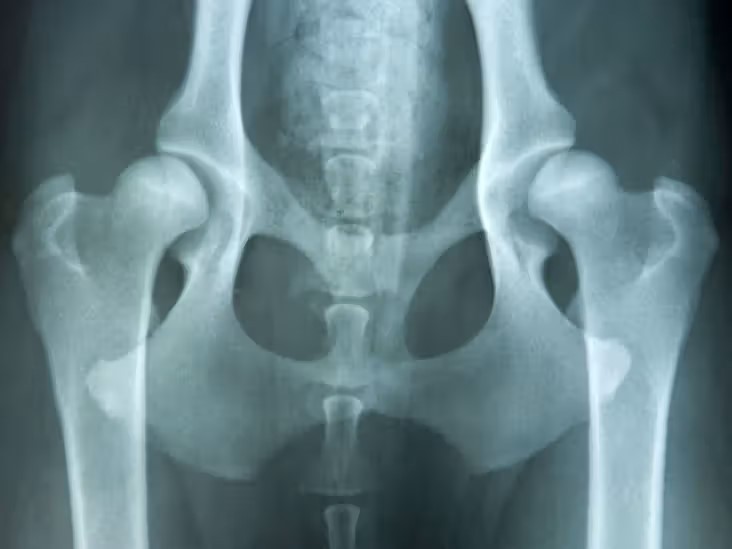

კოქსართროზი - რას მოიცავს კონსერვატიული მკურნალობა

კოქსართროზს - მენჯ-ბარძაყის სახსრის ოსტეოართროზი.